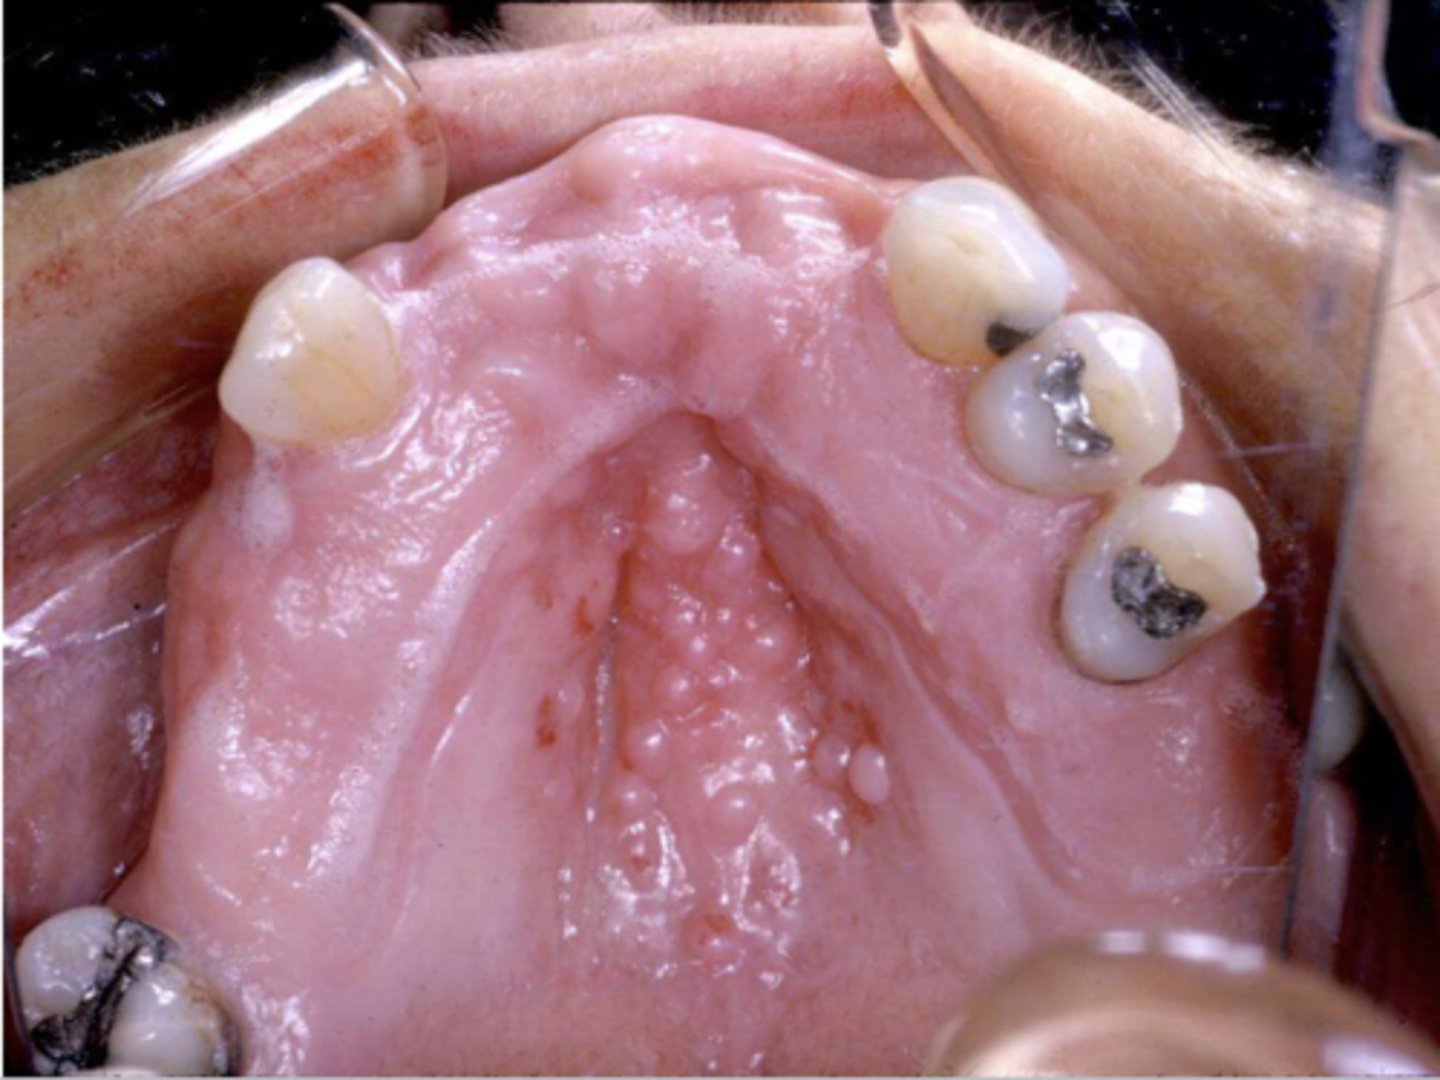

When the patient removed their complete maxillary denture, you see this. They reported wearing their denture to continuously throughout the day & night. What do you suspect?

inflammatory papillary hyperplasia w/ secondary candidal infection

*can tell pt also has candidiasis b/c of erythema

what are these clinical features of?

-hard palate beneath denture base

-pink or pebbly mucosa

-erythema --> suggests secondary candidal infection

inflammatory papillary hyperplasia